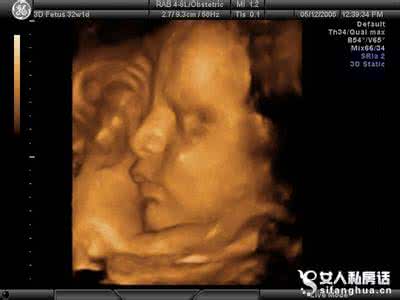

图2/3怀孕九个月四维彩超宝宝的脸

(2) B超检查,可以检测出胎儿双顶径大小,胎盘功能分级及羊水量等,评估出胎儿的发育状况。